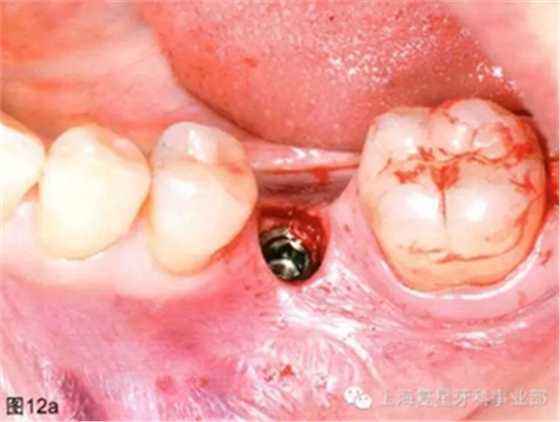

通過導(dǎo)板的引導(dǎo),以15prm,50Ncm旋入種植體。一旦種植體到達最后的深度(圖12a),去除種植手機和攜帶器,然后將一個愈合基臺(BioHorizons,直徑4.5毫米×長3毫米)擰在種植體上(圖12b)。軟組織打孔器取出的軟組織進行結(jié)締組織移植,然后放置在一個頰楔上獲得一定體積和厚度的角質(zhì)化軟組織(圖12c)。無需縫合。術(shù)后拍攝X片,對種植體的最終位置進行評估。

圖12a:種植體放置最終的位置上